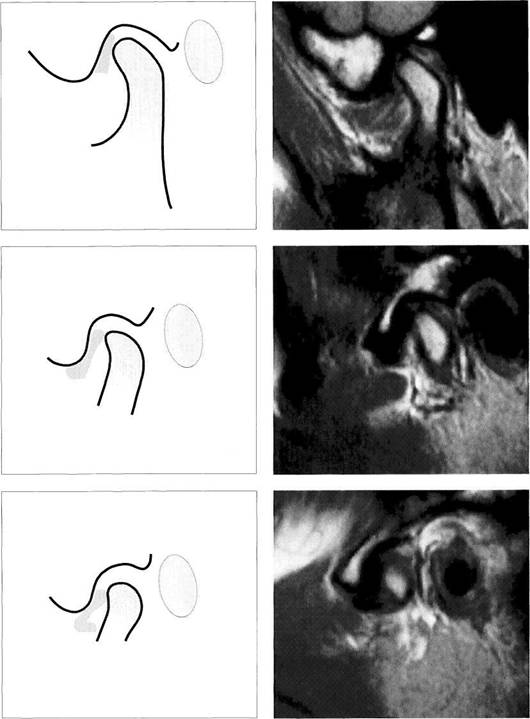

Disk Position in the Sagittal Plane

The disk position with the teeth in habitual occlusion is one of the most important parameters in visual MRI analysis. In the physiological position the disk lies with its pars inter­media in the region of the closest distance between the anterosuperior curvature of the condyle and the articular protuberance. From this position there can be a direct or definite displacement. If the posterior border of the pars posterior lies in front of a line representing the shortest distance between the condyle and the protuberance there is definite disk displacement. With this condyle-disk relation there will always be a clicking sound insofar as the disk can

reposition itself during jaw opening. As long as one part of the pars posterior still lies on the condyle, it is referred to as an insidious disk displacement or a tendency to disk displace­ment. A separate classification of disk position is made for each of the three joint sections (medial, central, and lateral).

Physiological disk position

Under normal conditions, the pars intermedia (*) of the disk lies be­tween the anterosuperior curva­ture of the condyle and the articular protuberance (arrows). The posi­tion of the posterior border of the pars posterior relative to the vertex of the condyle varies according to the inclination of the protuberance and is therefore not a reliable pa­rameter.

The arrows in this schematic draw­ing mark the relative positions of the condyle and the pars interme­dia to one another.

Insidious disk displacement or a tendency to anterior disk displacement

The pars intermedia lies well in front of the shortest distance be­tween condyle and protuberance (arrows), but the pars posterior (1) still lies on the condyle. Clinically, there are no clicking sounds during jaw opening.

Right: Drawing of a joint with a ten­dency to anterior disk displace­ment. The arrows mark the discrep­ancy between pars intermedia and condyle.

Definite disk displacement

Left: Both the pars intermedia (*) and the posterior border of the pars posterior lie in front of the most anterosuperior curvature of the condyle (arrows). Unless this is a case of disk displacement without repositioning, a clicking sound will occur regularly during jaw opening.

Right: Schematic drawing of a defi­nite anterior disk displacement. The arrows mark the discrepancy between the pars intermedia and condyle.